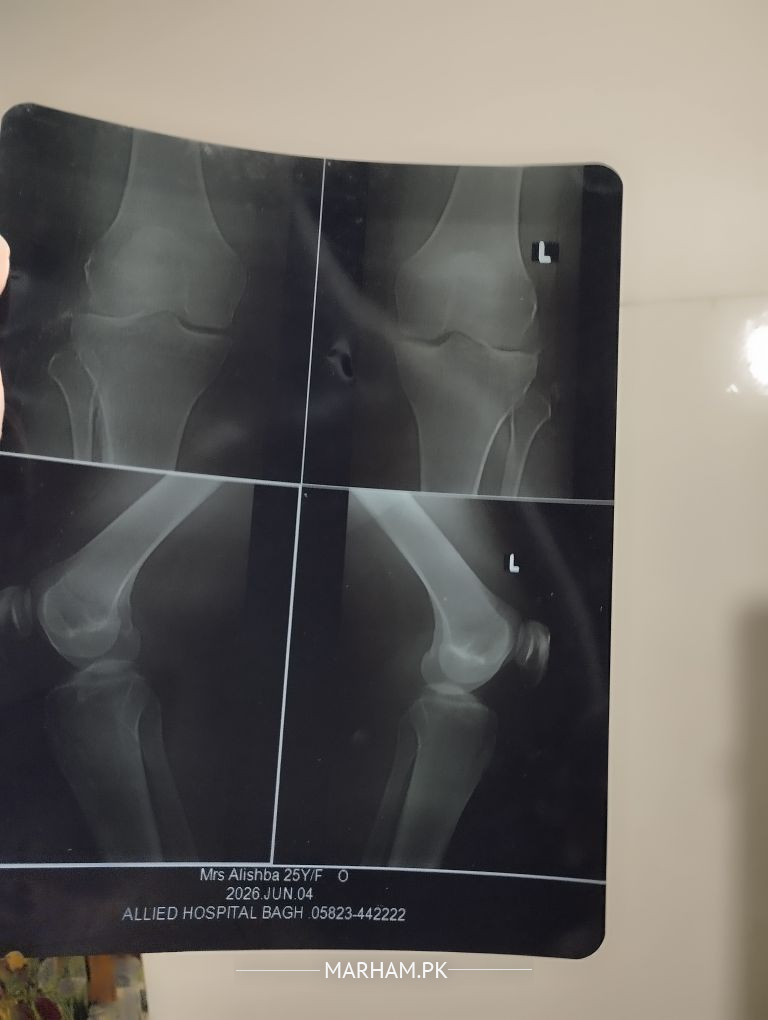

I've had a knee joint pain for Almost 2 months. I went to the Orthopedic surgeon yesterday, He did my x-ray and diagnosed a problem... I don't remember right now... also he gave some medication... can anyone here check my reports

There is decreased joint space in lateral compartment, at young age this could be due to inflammatory arthritis or septic arthritis if associated with fever and swelling. Important to assess clinically in face to face clinic and also review inflammatory markers

The xrays taken are not properly taken. the doctor might have told you early Osteoarthritis. For that we need xrays both knees AP standing view.

once You are too young for Osteoarthritis, other conditions can be excluded through investigations.